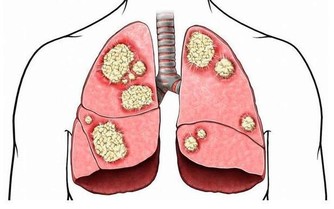

長期體內不間斷的惡性循環,久而久之就會導致致癌物在體內累積,引發各種癌症。

毒素蓄積的後果:皮膚粗糙,腹脹,腹痛,大腸癌!!

糞便留在腸道內,有害物質被再次吸收,可引起胃腸神經功能紊亂而致食欲不振、腸胃不適、腹部脹滿、口苦、肛門排氣多等表現,甚至可誘發結腸癌。